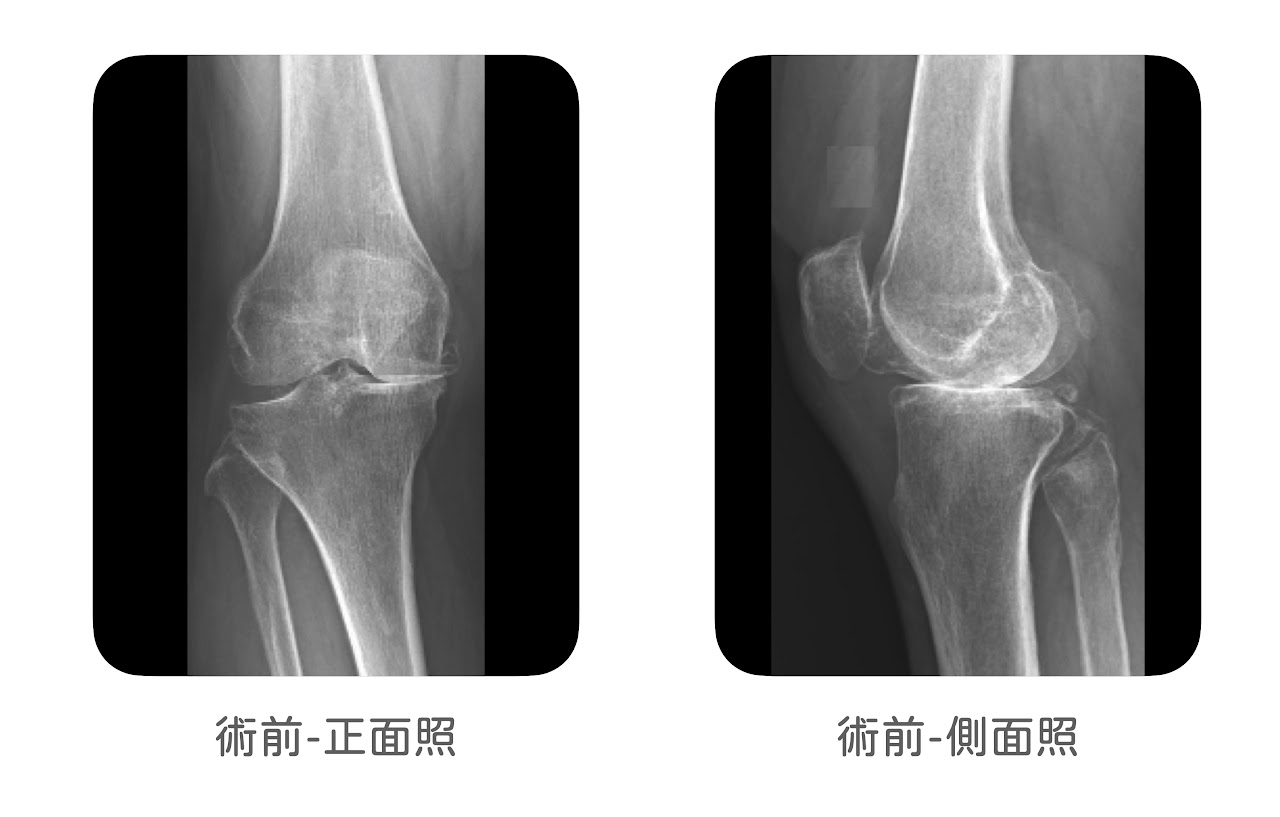

像是原本有厲害的 O 型腿合併內側關節炎(圖1),又或者是明顯的X型腿合併髕骨股骨關節脫臼(圖2),通常就不是部分人工關節置換手術適合處理的情況,所以部分人工膝關節置換手術,手術前需要確認角度沒有太大的偏差。

(圖1)